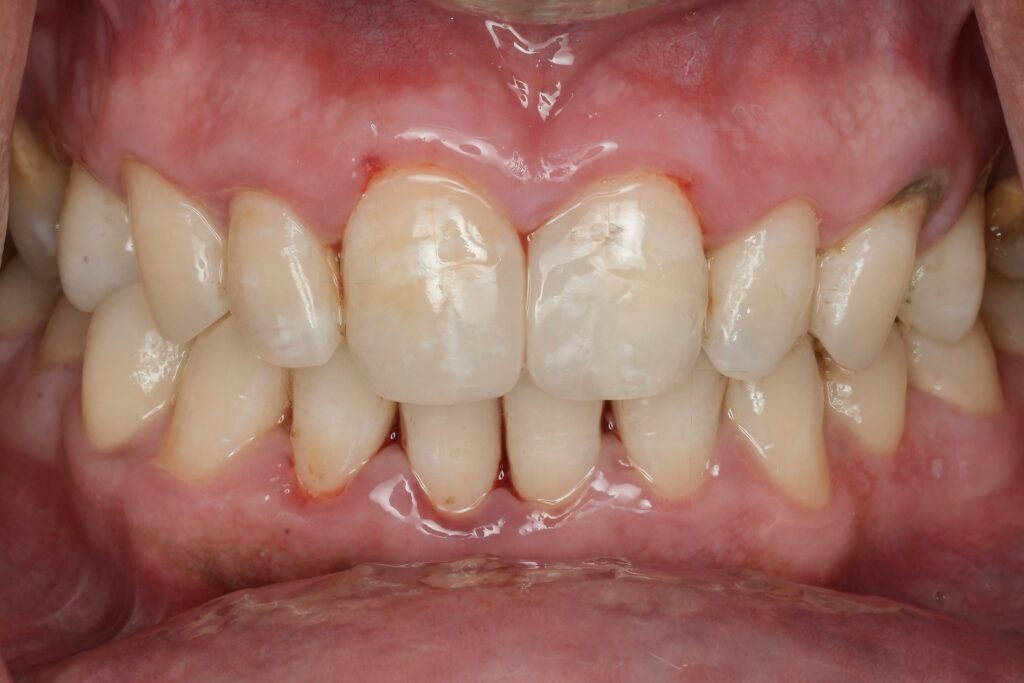

10) Finishing, polishing, and verification

- Remove the matrix, check contact with floss (snap + resistance)

- Adjust occlusion with thin paper (centric + excursions)

- Polish to reduce plaque retention and staining

- If available: photo documentation and a post-op bitewing for proximal seal/contact verification